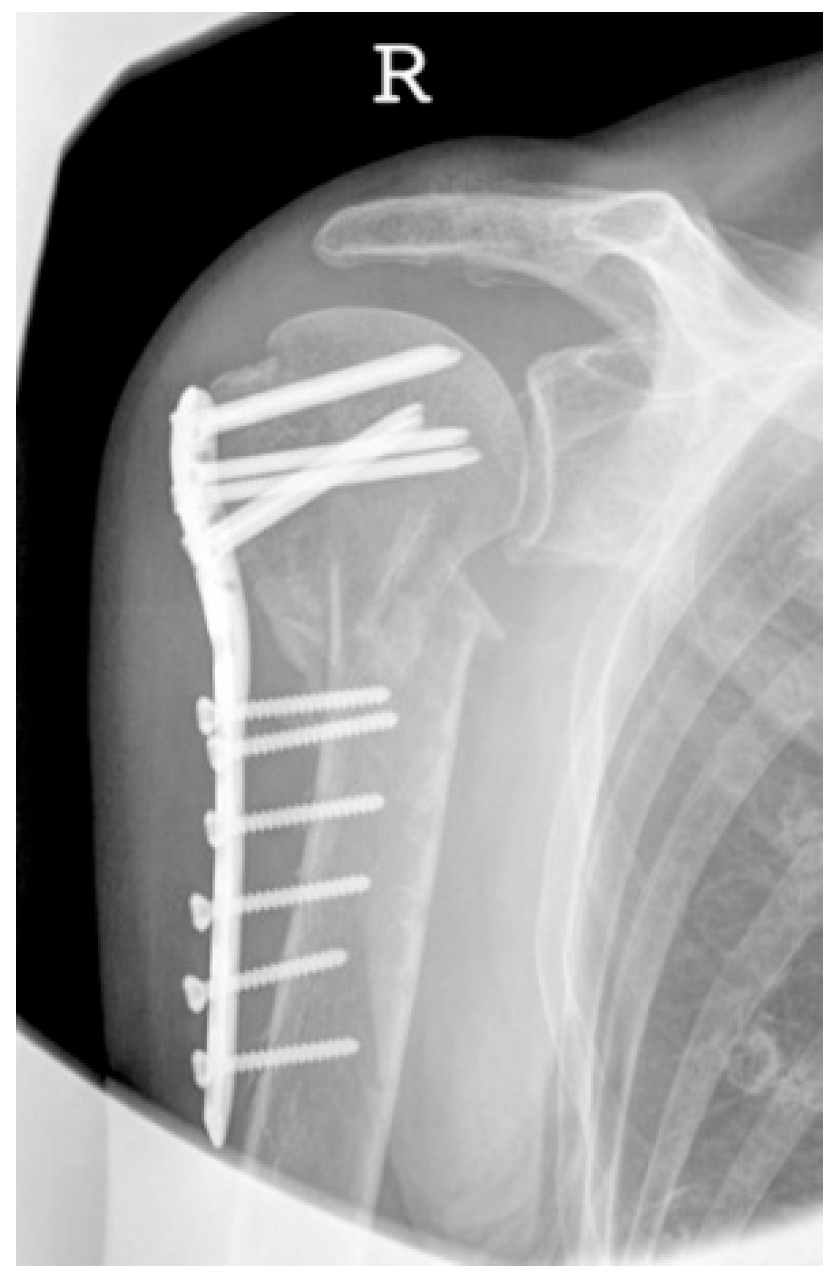

| Complication Type | Exemplary Images by X-rays or Pattern Images | Definition |

|---|---|---|

| 2c | ![]() | Type 2c is defined by a severe varus displacement (>20°) of the humeral head, which is associated with a screw cutout at the humeral head in parallel to Type 2a. In contrast to Type 2a, this varus displacement is characterized by an unstable osteosynthesis situation and progression. |